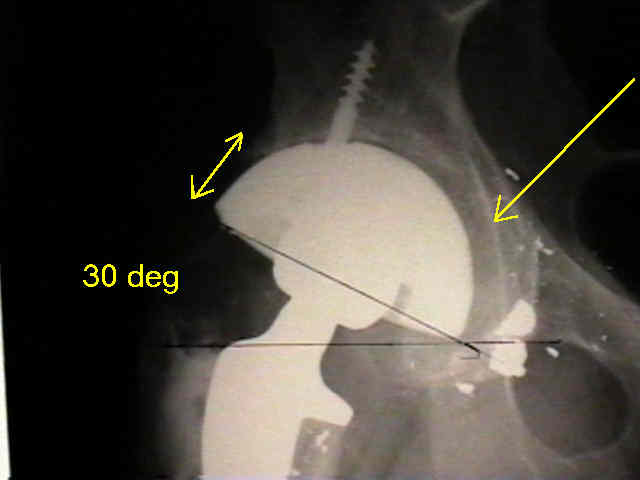

Case Example

- 35-year-old male w/ near anklyosed hip following a GSW to the hip;

- preoperative films appeared to indicate that little or no medialization was necessary;

- postoperative films, however, indicate that the cup was lateralized (hence, reaming was inadequate);

- in retrospect, the radiographs which are rotated externally (like an iliac oblique) tend to falsely minimize the necessary amount of medialization where as X-rays which are rotated internally (like an obturator oblique), tend to over-estimate the necessary amount of medialization